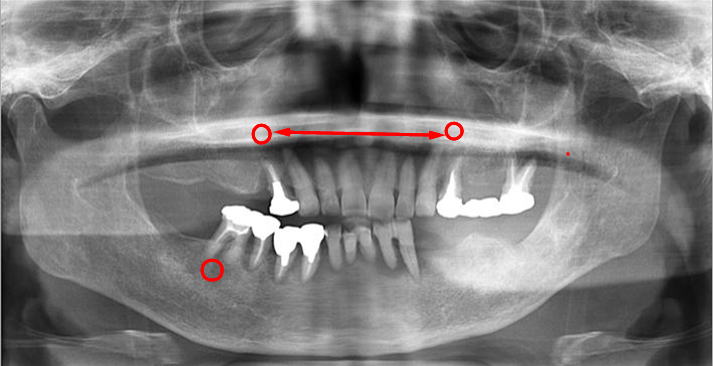

義歯が使えないとの主訴で来院されました。左右、前後、歯の高さは完全に崩壊。

この噛み合わせで義歯を作ったところで、噛み合わせはズレ、義歯を入れるスペースも不足(↕)しています。

義歯を新製はしたが「噛み辛い」「ガタつく」「痛い」は、咬合関係の崩壊を修正せず、基準を無視し新製してしまった症状と大いに考えられます。

しかし『咬合崩壊』の治療は困難であり、治療期間は長期に渡ります。

『咬合崩壊』は、ご自身に大いに責任があり、知らなかったでは済まされないのです。 |